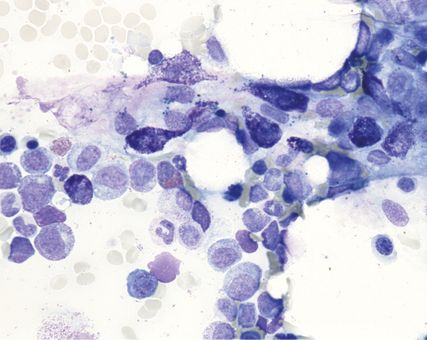

La cytologie permet d’évaluer la cellularité et les éventuelles dysplasies. En outre, il est important de quantifier les mastocytes, car un nombre ≥20% en dehors des fragments est considéré comme un critère de leucémie à mastocytes (MCL). En outre, un FACS est effectué sur le prélèvement de ponction de la moelle osseuse. Les analyses génétiques comprennent la détermination par génétique moléculaire de la mutation KIT-p.D816V avec charge mutationnelle («variant allele frequency», VAF) et par cytogénétique conventionnelle. Il n’existe toutefois aucune aberration spécifique à la MS, d’autant plus que celle-ci est rare pour la BMM et l’IMS.

Outre la quantification des mastocytes, la biopsie sert principalement à évaluer la présence d’infiltrats mastocytaires multifocaux et denses comme critère diagnostique majeur. Au-delà de la coloration, l’immunohistochimie est importante pour déterminer les mastocytes (tryptase, CD117, CD2, CD25, CD30) et mettre en évidence une éventuelle néoplasie hématologique associée (CD14, CD34, CD61).